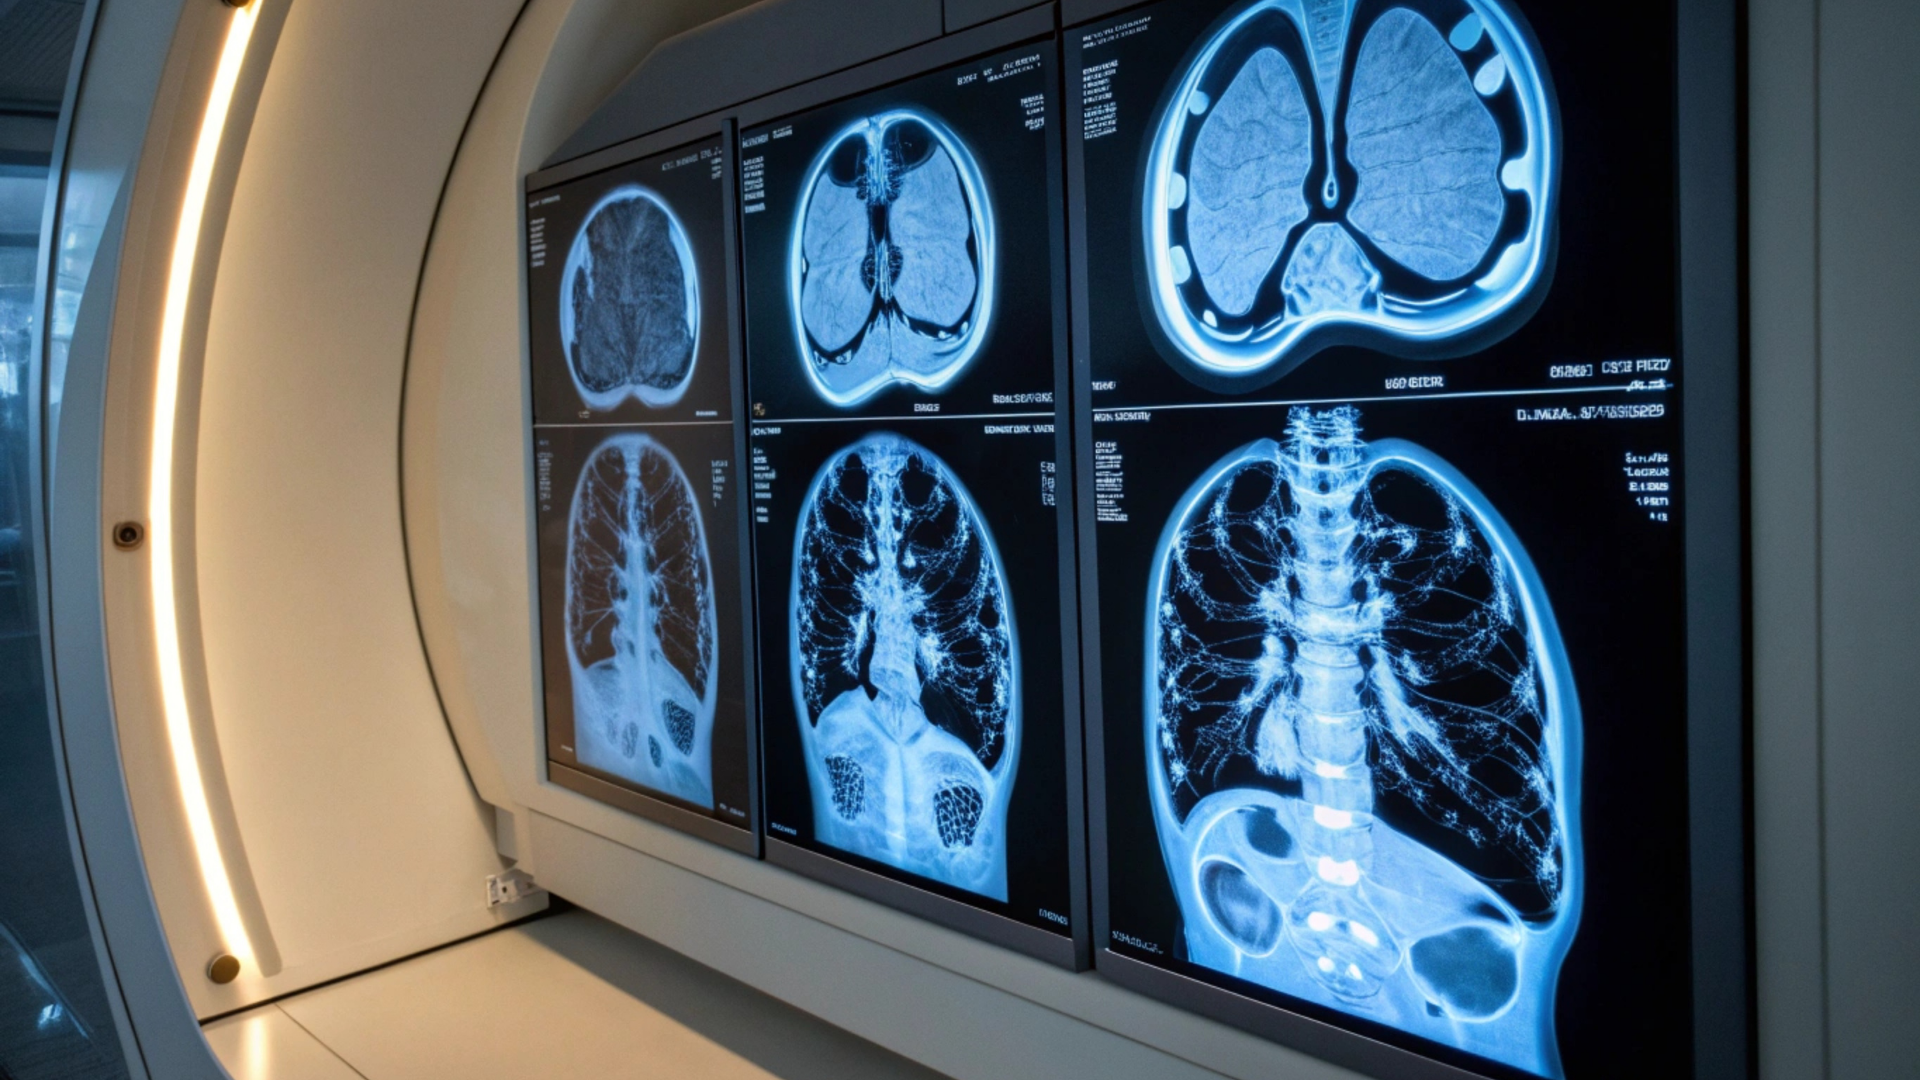

Chụp CT phổi (hay chụp cắt lớp vi tính lồng ngực) là phương pháp chẩn đoán hình ảnh chuyên sâu, cho phép quan sát chi tiết cấu trúc phổi, phế quản và các mạch máu bên trong lồng ngực. Đây được coi là "tiêu chuẩn vàng" để phát hiện những tổn thương mà phim X-quang thường có thể bỏ sót.

Những dữ liệu thô thu được từ máy CT sẽ được phần mềm xử lý thành hàng nghìn lát cắt siêu mỏng (độ dày chỉ từ 0.5 - 1mm). Từ các lát cắt này, bác sĩ sẽ dựng hình 3D toàn bộ lồng ngực, cho phép quan sát chi tiết từng ngóc ngách của nhu mô phổi, phế quản và các mạch máu nhỏ nhất. Điều này giúp không bỏ sót bất kỳ nốt mờ hay tổn thương mới nhú nào.